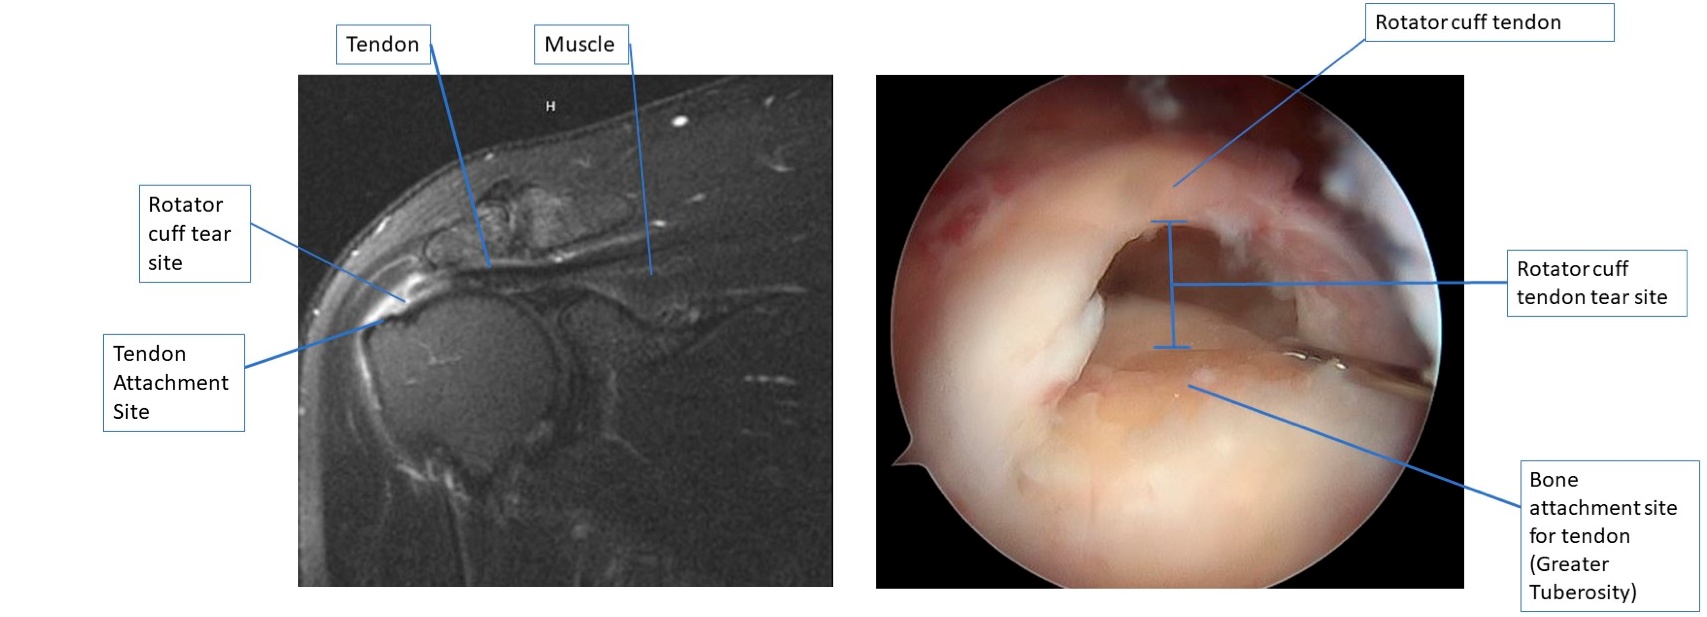

full thickness tear

A coronal MRI image on the left of a full thickness rotator cuff tear, and the same tear when viewed with an arthroscopic camera on the right.